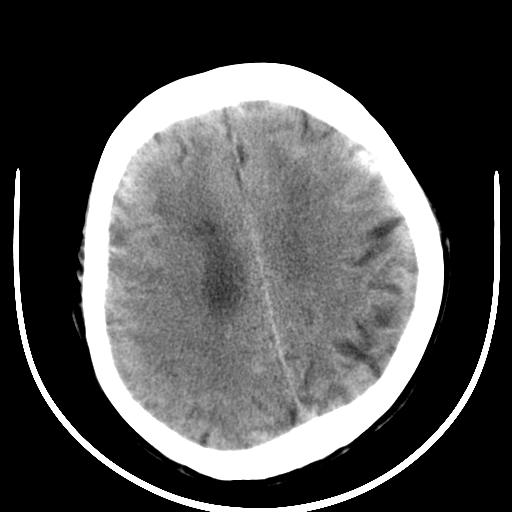

标题: CT16838:男58岁,意识不清2小时,请会诊出血部位该如何写。 [打印本页]

标题: CT16838:男58岁,意识不清2小时,请会诊出血部位该如何写。

呵呵  这样的做ct效果也太差了吧1首先 看见脑室扩大 1、左侧壳核出血。不足以解释临床的昏迷。

2、脑干区血肿。建议摆正位置 再来一次

图像质量太差,真不好确定,左基底结出血应该没有问题,再有就是蛛网膜下腔和脑干是否有出血,请老兄建议你们领导换机器吧

1)脑干、左侧桥小脑臂及小脑蚓部出血破入蛛网膜下腔。2)左侧基底节区灶性出血,不排除钙化灶。3)脑室系统少量积血。4)脑积水。

(患者病情危重,出现不自主运动——是引起图像质量不佳的主要原因)

脑干左侧原发性脑出血破入脑室系统及蛛网膜下腔出血伴梗阻性脑积水。左侧基底节区原发性脑出血。脑萎缩。

脑干左侧原发性脑出血破入脑室系统及蛛网膜下腔出血伴梗阻性脑积水。左侧基底节区像是钙化灶。轻度脑萎缩。

脑干左侧原发性脑出血破入脑室系统及蛛网膜下腔出血伴梗阻性脑积水。左侧基底节区原发性脑出血可能性大,钙化不除外。